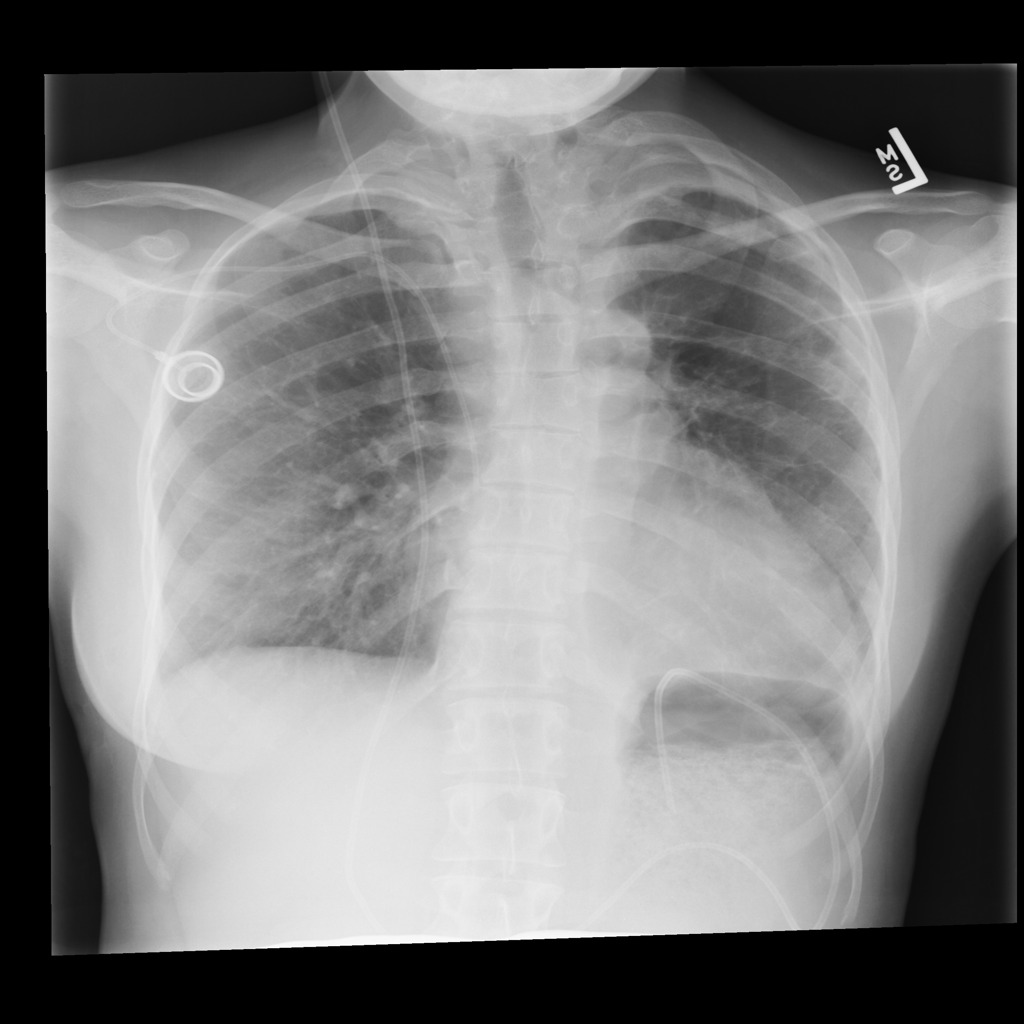

PAT-A380 · IMG-002Consolidation

PAT-A380 · IMG-002

AP